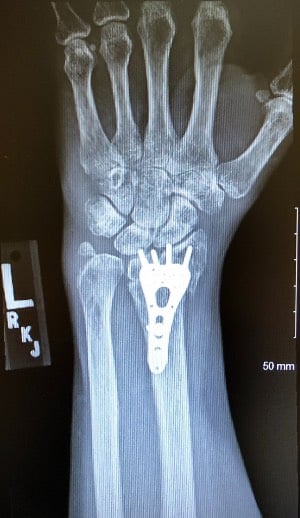

wrist fixed xray

X-ray of Tami's repaired wrist

Novant Health orthopedist Dr. James Romanowski arrived in about 15 minutes. Whiteside had a quick procedure to reposition part of her arm, a prelude to the surgery she’d face in a few days. She was wrapped up, braced and wheelchaired out, where Beau was waiting with the car running.

Thirty-six hours after the accident, Romanowski (“My hero,” Whiteside said) surgically repaired her wrist and arm. She said she spent a week being “one-handed,” then began recovery work with Novant Health occupational therapist Sarah Reymann to regain range of motion, strength and flexibility in her arm.